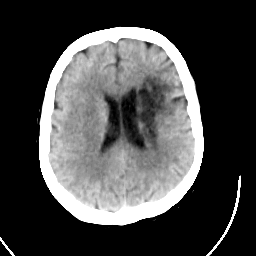

CT Study #1 -- Slice #16